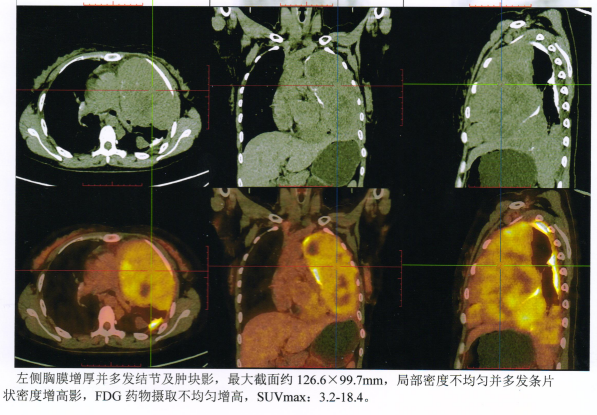

Left pleural thickening with multiple nodules and masses, the largest cross-section measuring approximately 126.6 × 99.7 mm, with inhomogeneous local density and multiple strip-like areas of increased density. FDG uptake is inhomogeneously increased, SUVmax: 3.2–18.4.

Liu Q, female, 34 years old. In May 2022, due to chest tightness and shortness of breath, she was found to have multiple left pleural nodules. She visited Tianjin Cancer Hospital, where a chest CT showed multiple left pleural nodules, the largest measuring approximately 3.2 × 2.1 cm. The patient underwent ultrasound-guided needle biopsy; pathology revealed synovial sarcoma, Ki-67 (40%+), with SS18–SSX1 gene fusion. Tumor mutation burden was 1.99 mutations/Mb, and microsatellite status was stable. The patient received oral anlotinib targeted therapy for two months but developed chest tightness, shortness of breath, and fever. Chest CT showed a large left pleural effusion and left lung atelectasis. On September 19, 2022, she underwent video-assisted thoracoscopic partial resection of the left upper lobe, pleural debridement, and pleurodesis at the PLA General Hospital. Postoperative treatment with tislelizumab led to disease progression. On February 27, 2023, the patient enrolled in a clinical trial and received four cycles of sintilimab. On June 2, 2023, follow-up chest CT revealed thickening of the left pleura and interlobar pleura with multiple irregular nodules, larger than before, some confluent into masses, the largest measuring approximately 15.5 × 7.3 cm. On June 12, 2023, she enrolled in another Phase I clinical trial (CAN1012 intratumoral injection for safety, tolerability, and preliminary efficacy in patients with advanced solid tumors) and received two treatments, but the tumor was not effectively controlled. She then presented to the Wuwei Heavy Ion Center. PET-CT showed multiple nodules of thickened left pleura, the largest cross-section approximately 12.6 × 10 cm, SUVmax 18.4. She was admitted on July 26, 2023, and received heavy (carbon) ion radiotherapy, along with two cycles of concurrent sintilimab. During the initial phase of treatment, she experienced transient nausea and fatigue, which gradually improved. The treatment course was uneventful. After treatment, she developed grade 1 skin hyperpigmentation in the radiation field and grade 1 radiation esophagitis, both of which improved with symptomatic management. No other radiation-related adverse effects were observed. Follow-up chest CT after treatment showed that the left pleural and interlobar pleural nodules had significantly reduced in size, with the largest measuring approximately 10 × 4.1 cm. The patient achieved a partial response (PR) to treatment. Midway through her treatment, specifically after the ninth fraction, a follow-up CT scan revealed that the 10 cm tumor had shrunk considerably. In Ms. Liu's own words, it was "incredible, unbelievable, that it could shrink so much."